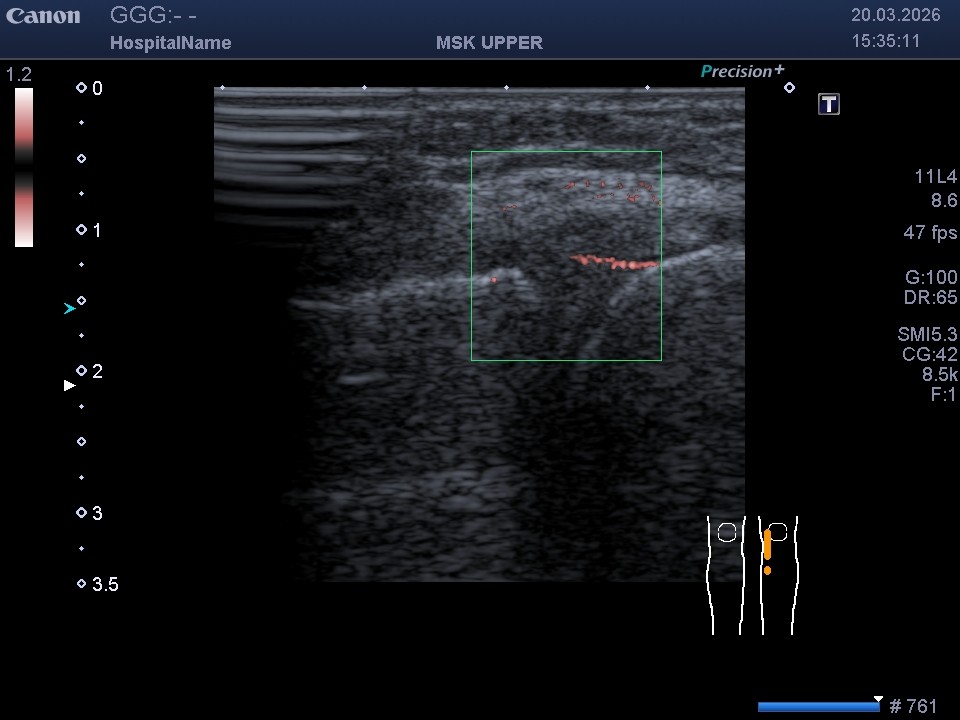

- Технологія SMI (візуалізація мікроциркуляторного русла): Це унікальний режим, що дозволяє побачити найдрібніші судини. Завдяки SMI ми можемо визначити кровопостачання «червоної зони» меніска та зафіксувати рідкісне явище — неоангіогенез (появу нових судин) у «білій зоні» після травми.

Розриви в червоній зоні (де є кровопостачання) загоюються набагато швидше. Біла зона позбавлена судин, тому відновлення там проходить важче. На звичайному УЗД (В-режимі) відрізнити ці зони неможливо, але режим SMI дозволяє відмежувати їх завдяки доплерівському сигналу від мікросудин.